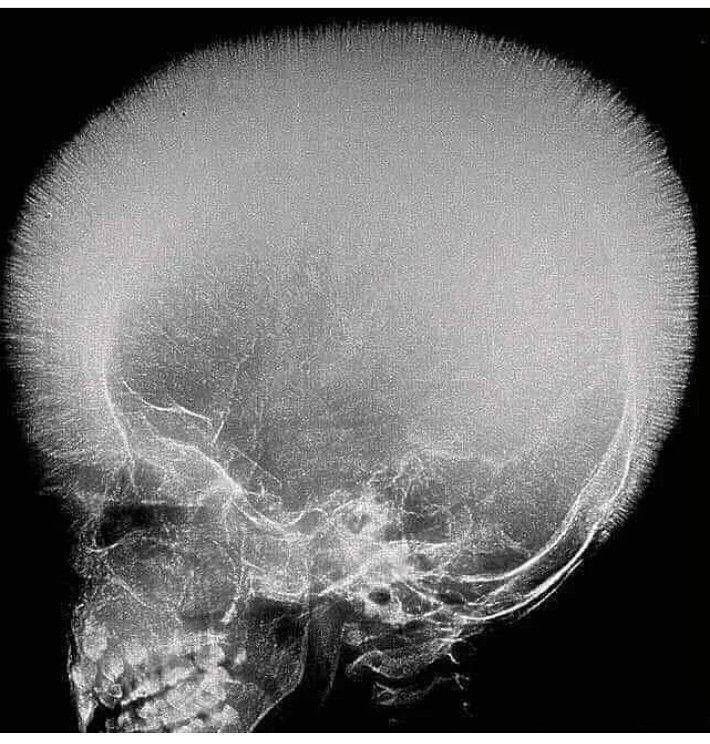

Crew cut/ Hair-on-end' sign is seen in the diploic spaces on the skull radiographs appearing like long, thin vertical striations that resemble hairs standing on ends. Hair-on-end appearance of the skull is a characteristic feature of chronic hemolysis usually seen in patients with thalassemia and sickle cell anemia.